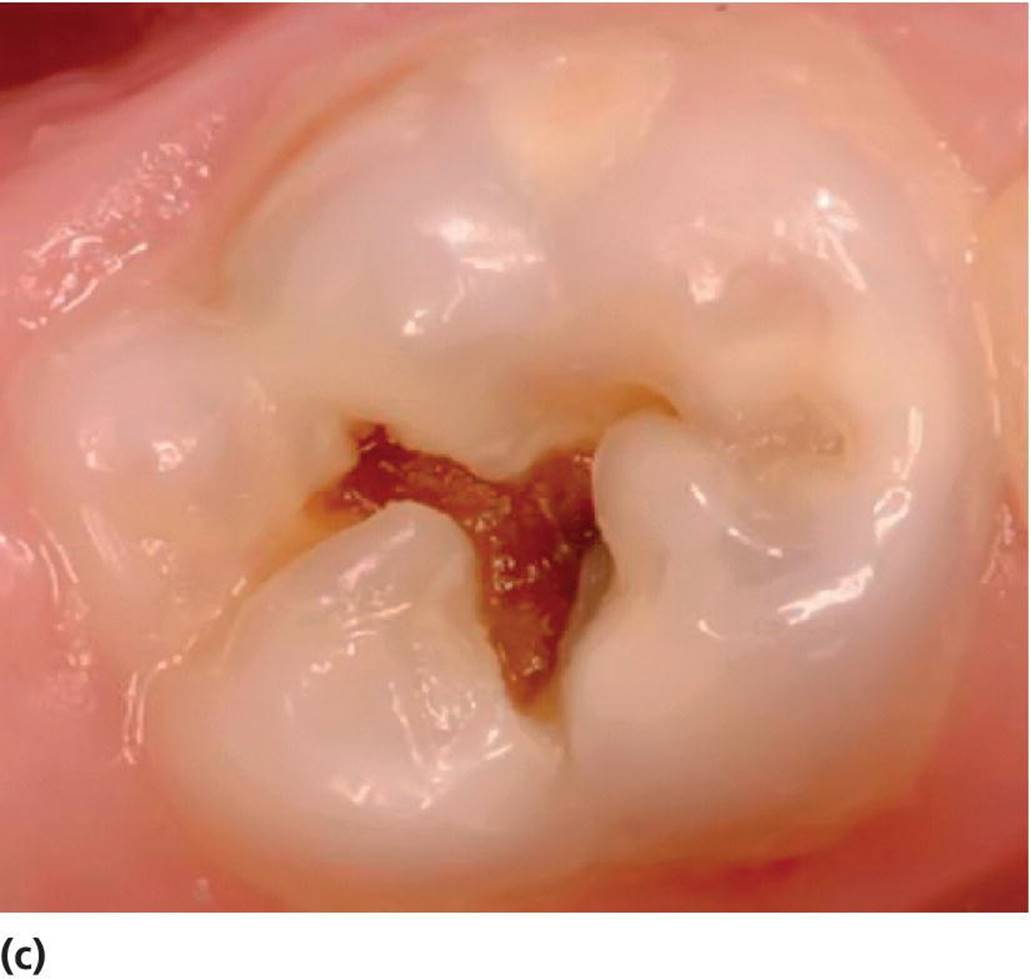

Assessment of lesion activity is as important as lesion detection. Criteria for active and inactive caries lesions slightly modified after Nyvad et al. [7] and Ekstrand et al. [8] are presented in Box 12.3. Figure 12.3illustrates active and arrested lesions.

Figure 12.3 Active and inactive/arrested caries lesions. Upper row shows initial (noncavitated lesions) and the lower row shows cavitated lesions. (a) Active noncavitated lesions close to the gingival line on the buccal surfaces of primary upper incisors in a 2‐year‐old. There is loss of luster and the lesions are rough on probing. (b) Arrested noncavitated lesions on the buccal surfaces of primary upper incisors in a 4‐year‐old. The lesions are situated at a distance from the gingival line, and are shiny and hard on probing. (c) Active cavitated lesion in a primary lower second molar in a 5‐year‐old. The dentin is soft on probing and the cavity borders are blunt and irregular. (d) Inactive/arrested cavitated lesion in a primary lower first molar in a 7‐year‐old. The dentin is brownish‐black, hard on probing, and the cavity borders are sharp and regular.